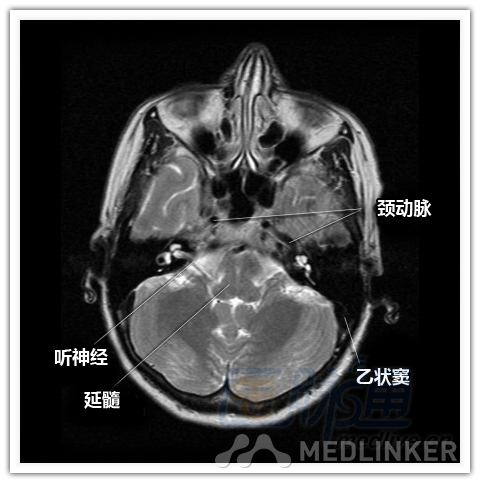

简明易懂的脑部断层解剖:横断位MRI(1)

本文将对不同横断位的脑部MRI图像进行标示,主要讲解内容是脑部基本解剖。脑部横断位解剖,尤其是内囊层面的影像学解剖一直是一大重点,一起来学习一下。 横断位图像顺序:由足侧至头侧 本文转载自医脉通。 声明:本文转载是出于提供更多信息以参考使用或学习、交流之目的,不用于商业用途。转载无意侵犯版权,如转载文章涉及您的权益等问题,请作者速来告知,我们将尽快做删除处理。